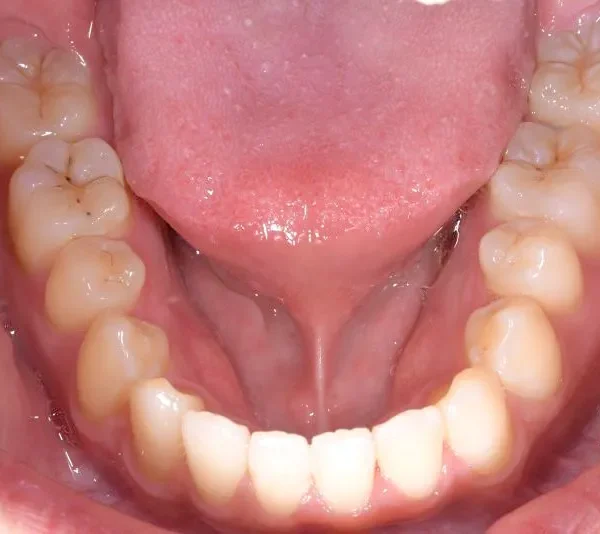

【大人の矯正】叢生・八重歯・交叉咬合・非抜歯症例・19歳女性【R.T様】

初診時年齢 19~29歳 (女性) 主訴 ガタガタ・交叉咬合が気になる

診断名 叢生・交叉咬合 装置名

矯正用アンカースクリュー4本・マルチブラケット矯正装置

抜歯の有無 非抜歯 治療期間・通院回数 3年 1ヶ月 / 42回

ガタガタ・八重歯を主訴に来院された患者様です。

初診